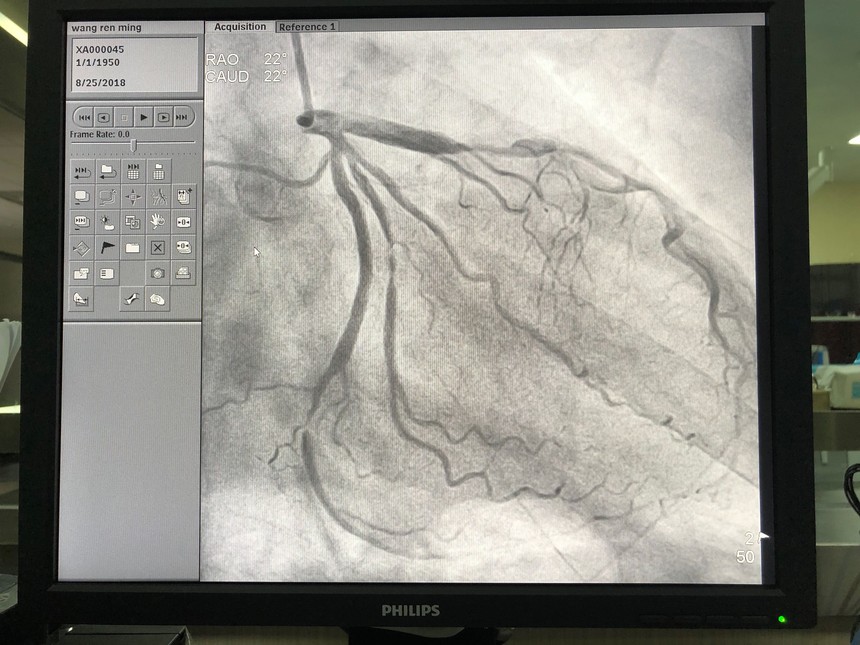

心血管介入中心(DSA)我院心血管介入中心(DSA)于2018年5月創(chuàng)建。在浙大二院長駐和短期10余名幫扶專家的指導(dǎo)下,冠脈造影技術(shù)已成為我院常規(guī)檢查手段,檢查治療病人已超100例,急救了4例急性心肌梗死病人,均未出現(xiàn)如同造影劑過敏、心律失常、動靜脈瘺、冠脈穿孔及心包填塞等嚴重并發(fā)癥。 數(shù)字減影血管造影(DSA)的基本原理是將注入造影劑前后拍攝的兩幀X線圖像經(jīng)數(shù)字化輸入圖像計算機,通過減影、增強和再成像過程來獲得清晰的純血管影像,同時實時地顯現(xiàn)血管影。DSA具有對比度分辨率高、檢查時間短、造影劑用量少,濃度低、患者X線吸收量明顯降低以及節(jié)省膠片等優(yōu)點,在血管疾患的臨床診斷中,具有十分重要的意義。目前臺江縣人民醫(yī)院心臟介入中心配置一臺飛利浦數(shù)字減影血管造影機,有浙大二院心內(nèi)科專家長期幫扶和支持,能開展經(jīng)皮冠狀動脈造影術(shù)、經(jīng)皮冠狀動脈血管成型術(shù)及經(jīng)皮冠狀動脈支架置入術(shù)。

經(jīng)皮冠狀動脈手術(shù)

術(shù)前